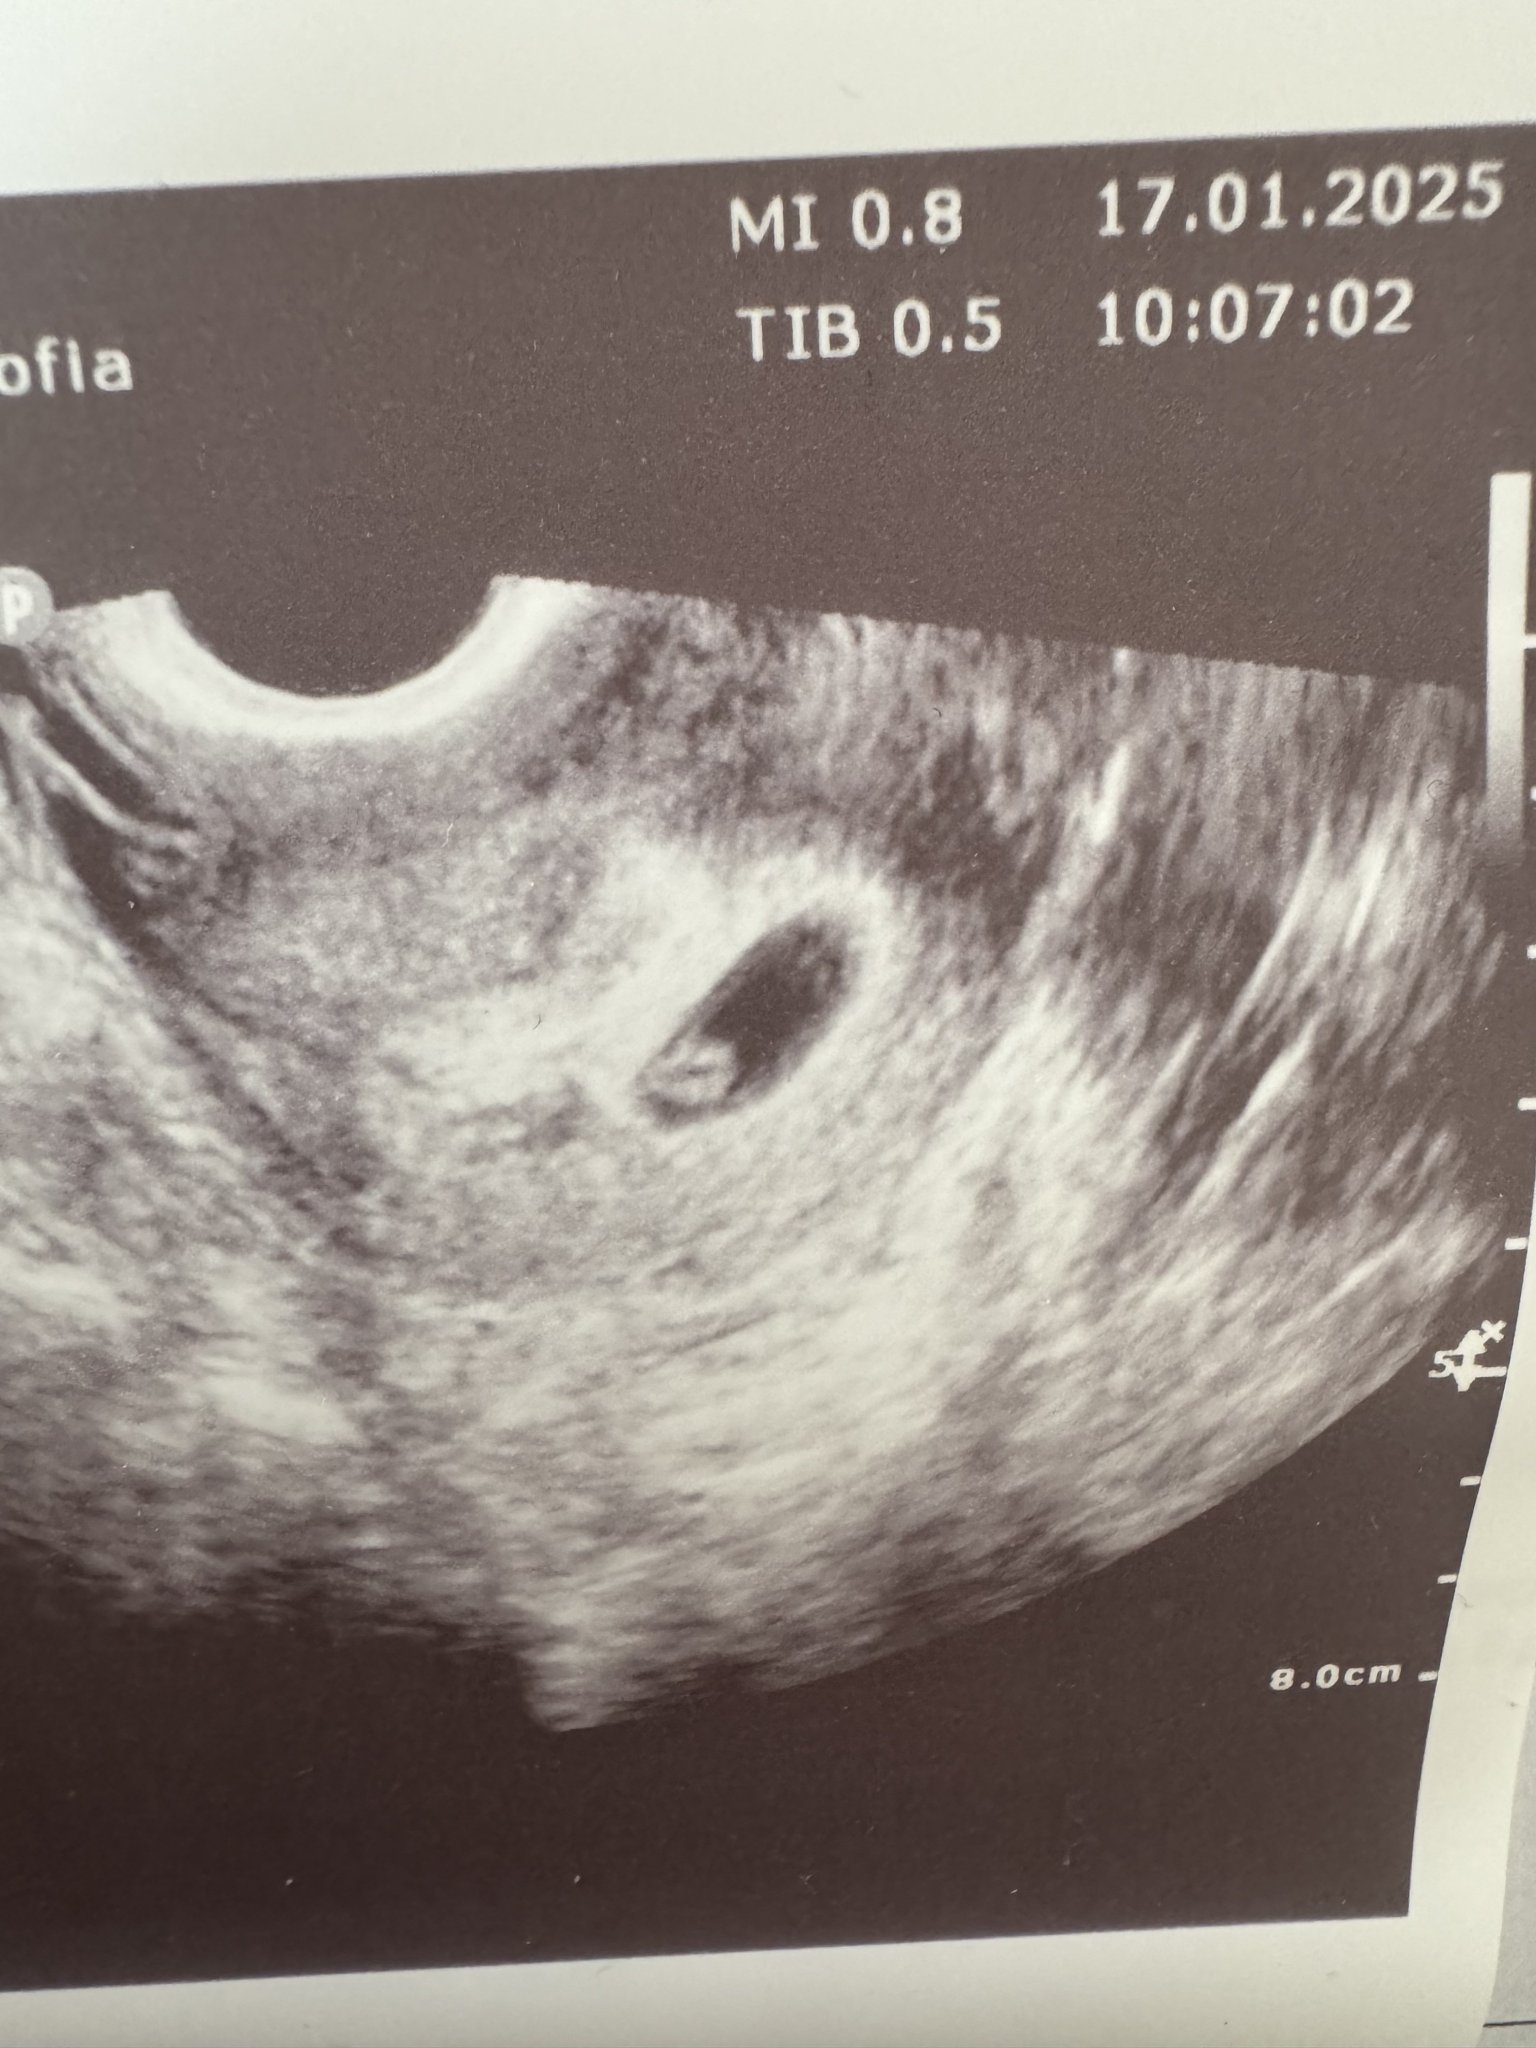

Какво представлява изображението от ехографията на 5-седмична и 2-дневна бременност?

Какво представляват черните точки в матката на ехографската снимка?